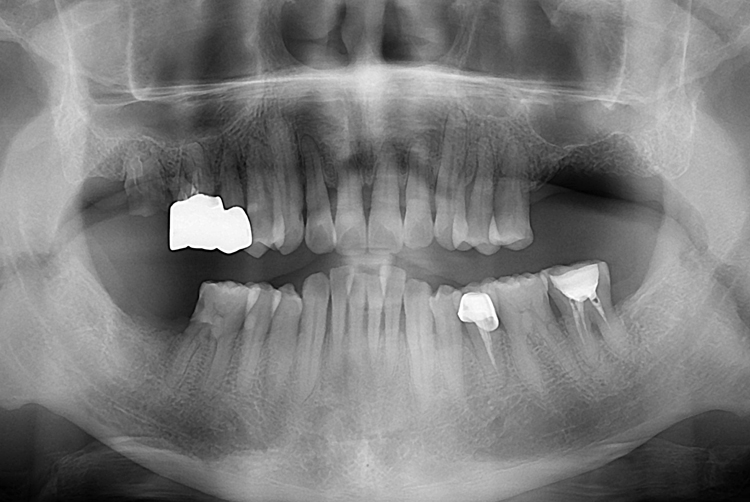

[임플란트] 어금니 임플란트

치료후 : 2017-08-02

세종치과는 많은 환자와 다양한 케이스를 바탕으로

항상 편안한 임플란트 수술을 제공하고자 노력하고,

오래동안 튼튼히 쓸 수 있는 임플란트 수술을 가장 큰 목표로 삼고 있습니다.